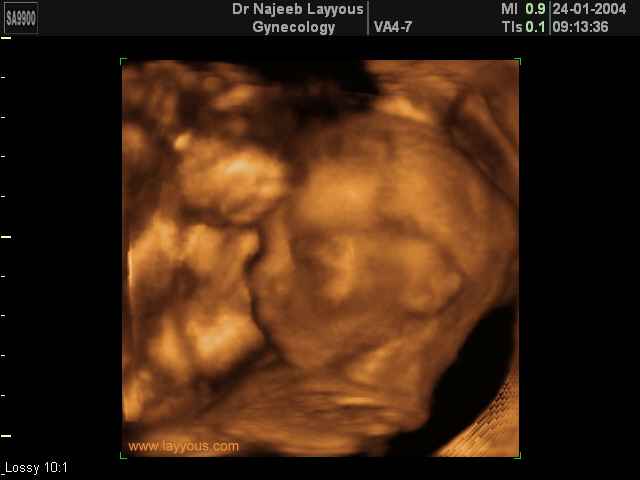

- Fetal Behavior Ultrasound Photos

3D Second Trimester Ultrasound Scan Photos-second part of pregnancy | Dr N Layyous